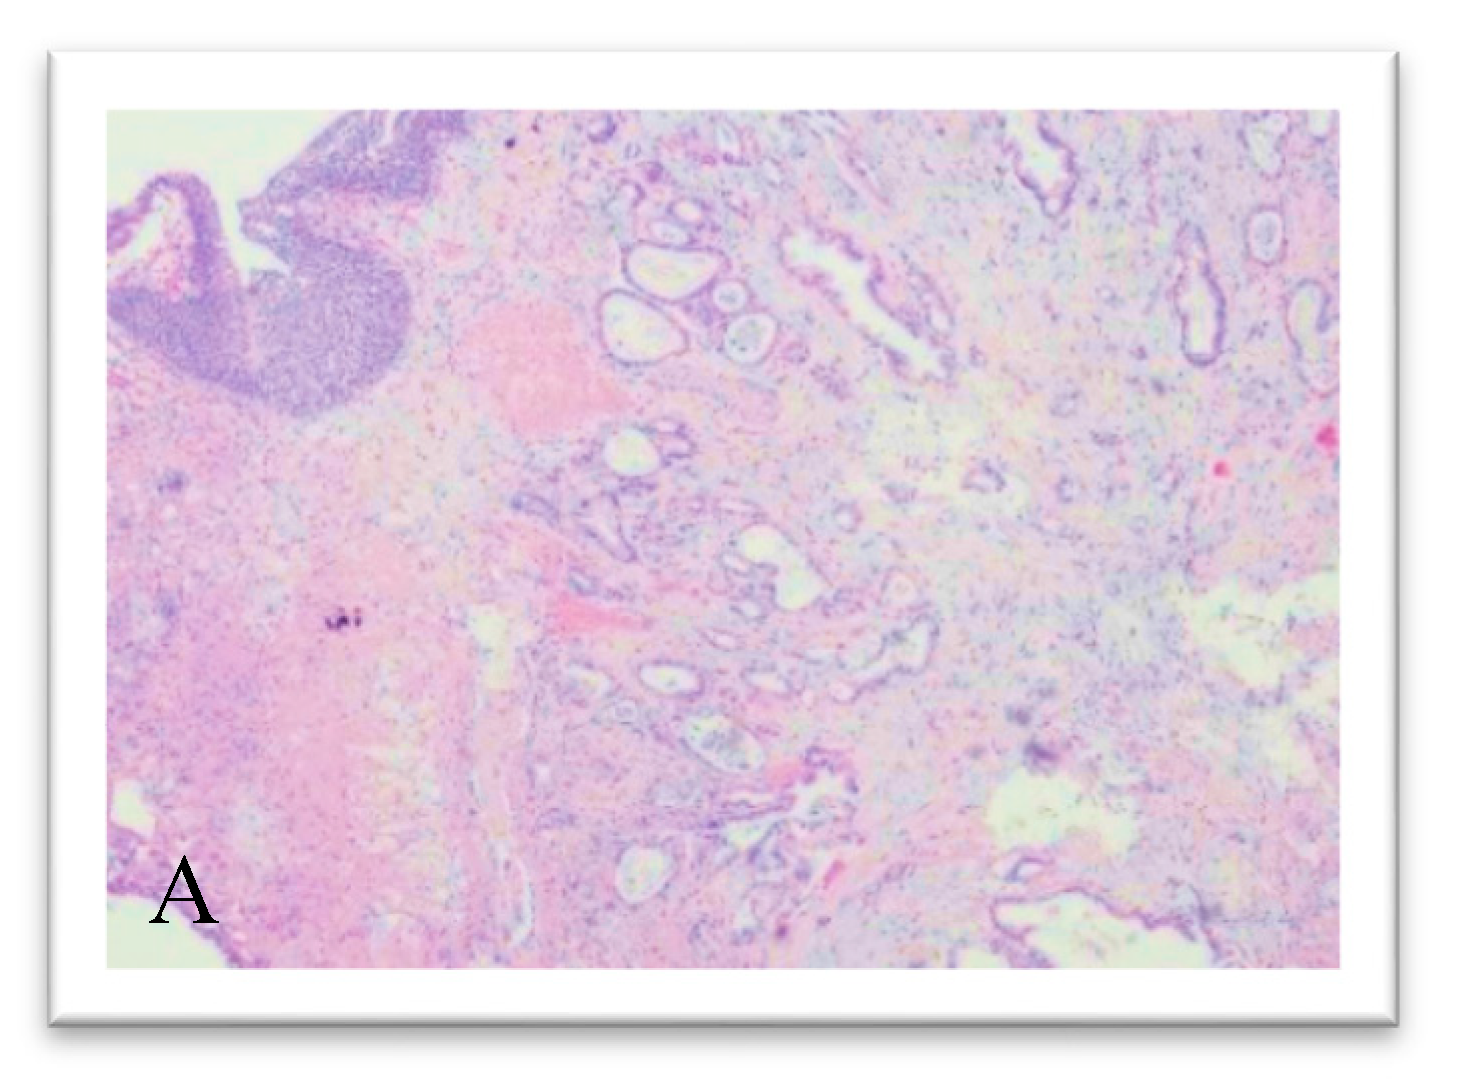

2. Case Presentation